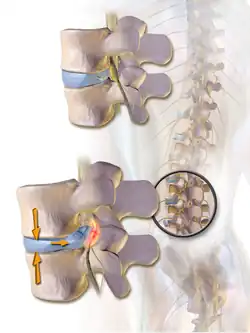

Herniated disc pressing on spinal nerves.

Spinal fusion can be used to treat a variety of conditions affecting any level of the spine—lumbar, cervical and thoracic. In general, spinal fusion is performed to decompress and stabilize the spine.[4] The greatest benefit appears to be in spondylolisthesis, while evidence is weaker for spinal stenosis.[5]

The most common cause of pressure on the spinal cord/nerves is degenerative disc disease.[6] Other common causes include disc herniation, spinal stenosis, trauma, and spinal tumors.[4] Spinal stenosis results from bony growths (osteophytes) or thickened ligaments that cause narrowing of the spinal canal over time.[4] This causes leg pain with increased activity, a condition called neurogenic claudication.[4] Pressure on the nerves as they exit the spinal cord (radiculopathy) causes pain in the area where the nerves originated (leg for lumbar pathology, arm for cervical pathology).[4] In severe cases, this pressure can cause neurologic deficits, like numbness, tingling, bowel/bladder dysfunction, and paralysis.[4]